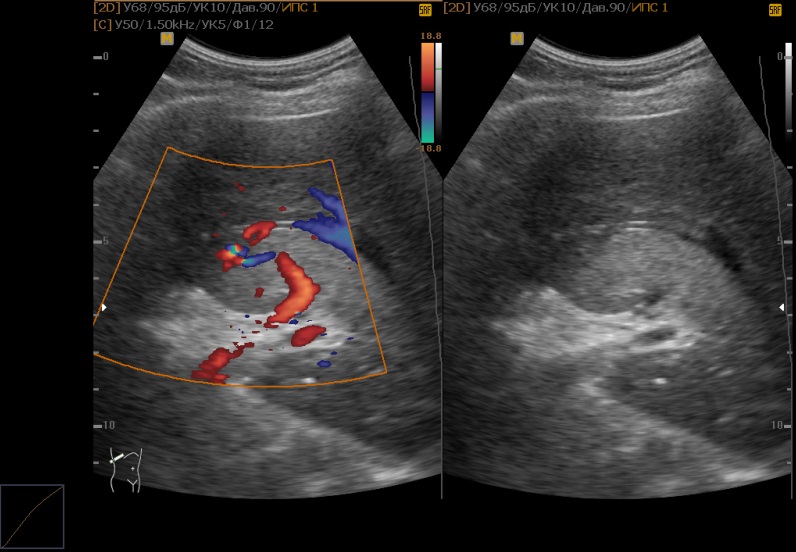

Диагностика

Чтобы поставить правильный диагноз, требуется выполнение инструментальных диагностических методов:

- Ультразвуковое исследование. Метод визуализации органов и анатомических структур. В его основе лежит использование высокочастотных звуковых волн, которые отражаются от органов с формированием изображения.